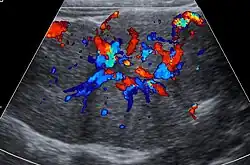

Lorsqu’elle est visible, la cicatrice centrale est hyperéchogène[1],[3],[12] (mais possiblement hypoéchogène [6]). L’étude en Doppler couleur permet de visualiser au centre de la lésion une hypervascularisation traduisant la présence de l’artère afférente[12].

L’étude en Doppler pulsé met en évidence des vitesses systoliques élevées[6],[12] et un index de résistance d’environ 0,5[1],[3].